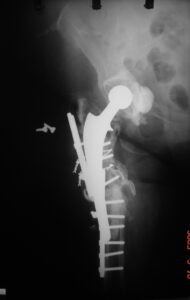

- Περιπροθετικό κάταγμα στην περιοχή του ισχίου στο επίπεδο του εμφυτεύματος.

- εσωτερική οστεοσύνθεση με πλάκα και αρκετή ελαστικότητα στο σύστημα.

- Ο ασθενής είναι σε πλήρη δραστηριότητα σε διάστημα δυόμισι μηνών μετά το κάταγμα.

- Περιπροθετικό κάταγμα στην περιοχή στο πέρας του εμφυτεύματος ισχίου σε θήλυ ασθενή .

- Εσωτερική οστεοσύνθεση με πλάκα με αλληλοεπικάλυψη των εμφυτευμάτων για να μην υπάρχουν υψηλές συγκεντρώσεις φορτίων (stress risers)

- H οστεοσύνθεση σε οστεοπορωτικoύς ασθενείς αρχίζει από το γόνατο με σωστή εφαρμογή του εμφυτεύματος και φθάνει μέχρι το ισχίο για να μην υπάρχουν stress risers.

Tα περιπροθετικά κατάγματα σε ηλικιωμένους πρέπει στην οστεοσύνθεση να περιλαμβάνουν ολόκληρο το μήκος του οστού, με αρκετή ελαστικότητα, προάγοντας έτσι την πώρωση και διατηρώντας ταυτόχρονα την σταθερότητα του συστήματος.